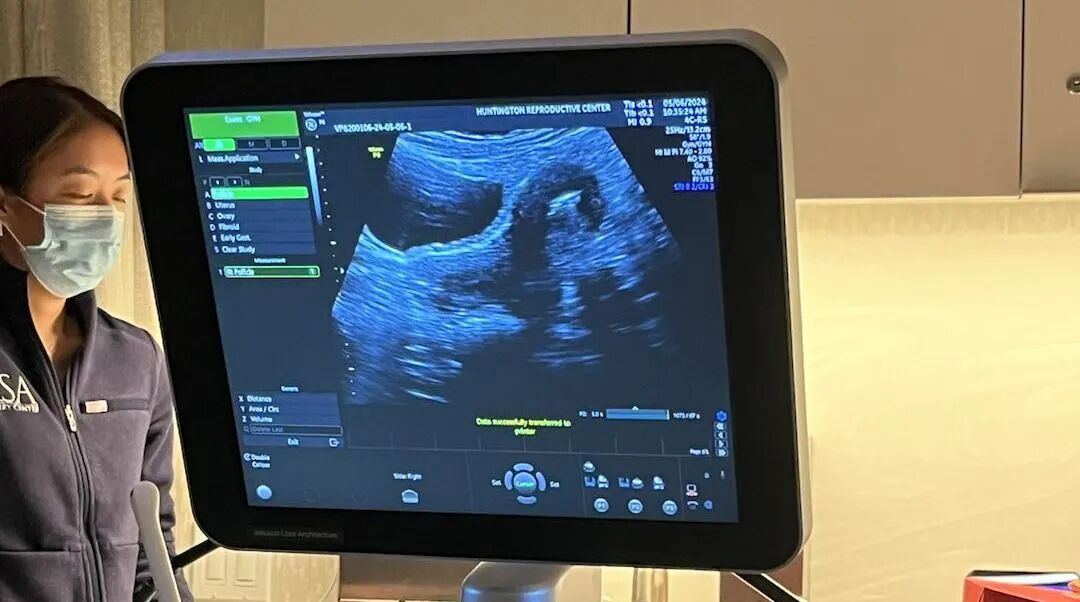

祝贺爱妈K迎来了她的移植日!这是一个令人激动的里程碑,尤其是对于期待已久的加拿大准父母来说!爱妈K来自俄勒冈州,已经有两个可爱的女儿。虽然她曾在邮局工作,但她一直认为做母亲是她最重要的职责,所以成为一名爱妈也是非常光荣的一件事情。

我们的准父母是使用了自己的精子和卵子制造出了高质量的胚胎。在爱妈的准备过程中,检非常顺利,但在第一次移植中由于子宫内膜厚度不达标,不得不取消了那个周期。经过专家们的谨慎调整和精心准备,她的子宫内膜终于达到了移植的标准,这次移植也非常顺利地完成了。爱妈K和准父母共同期待着好消息。为他们的旅程送上最美好的祝愿,并期待听到更多的更新!